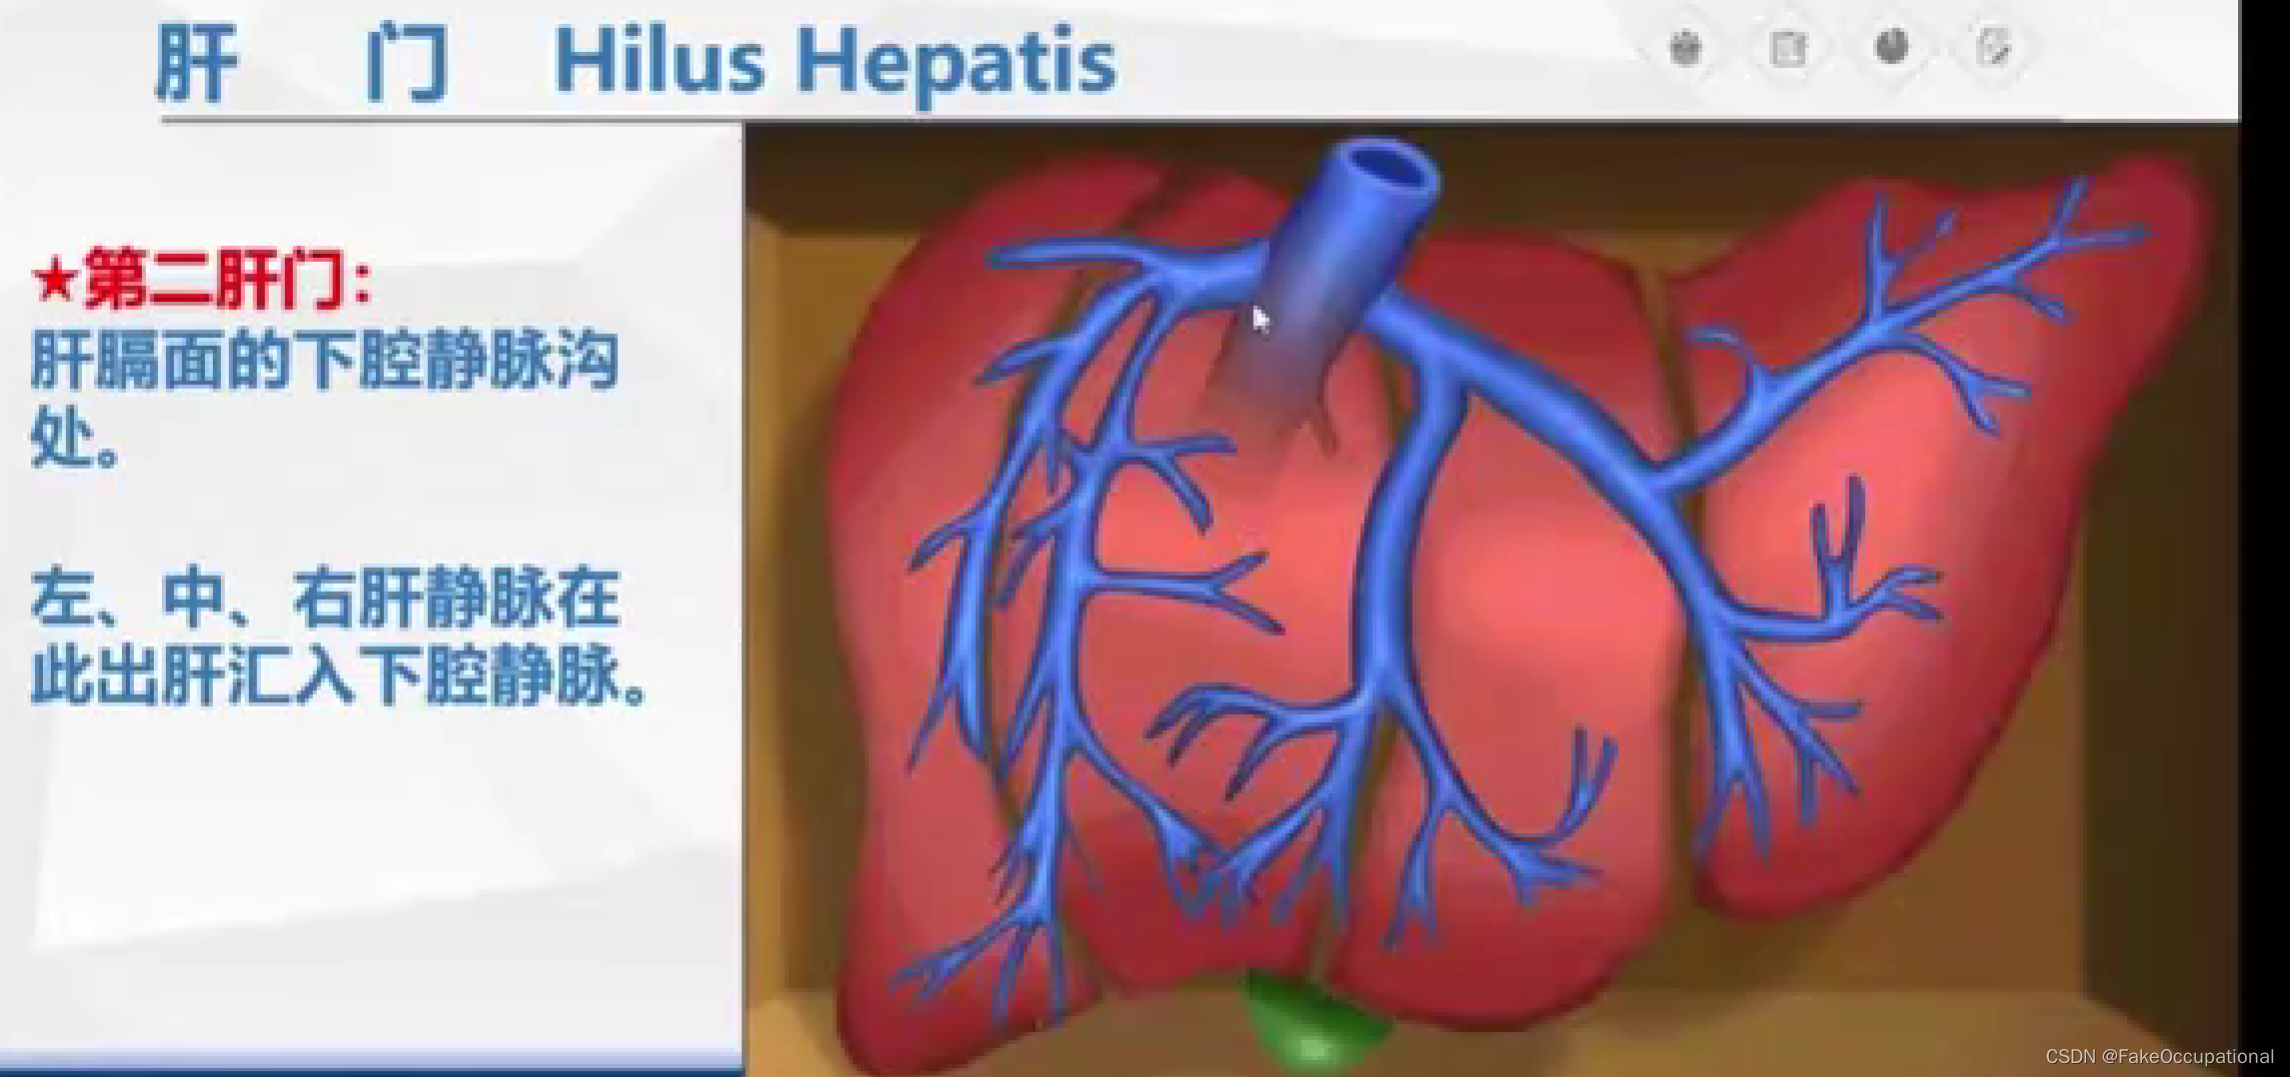

肝脏解剖概要

肝脏超声检查技术